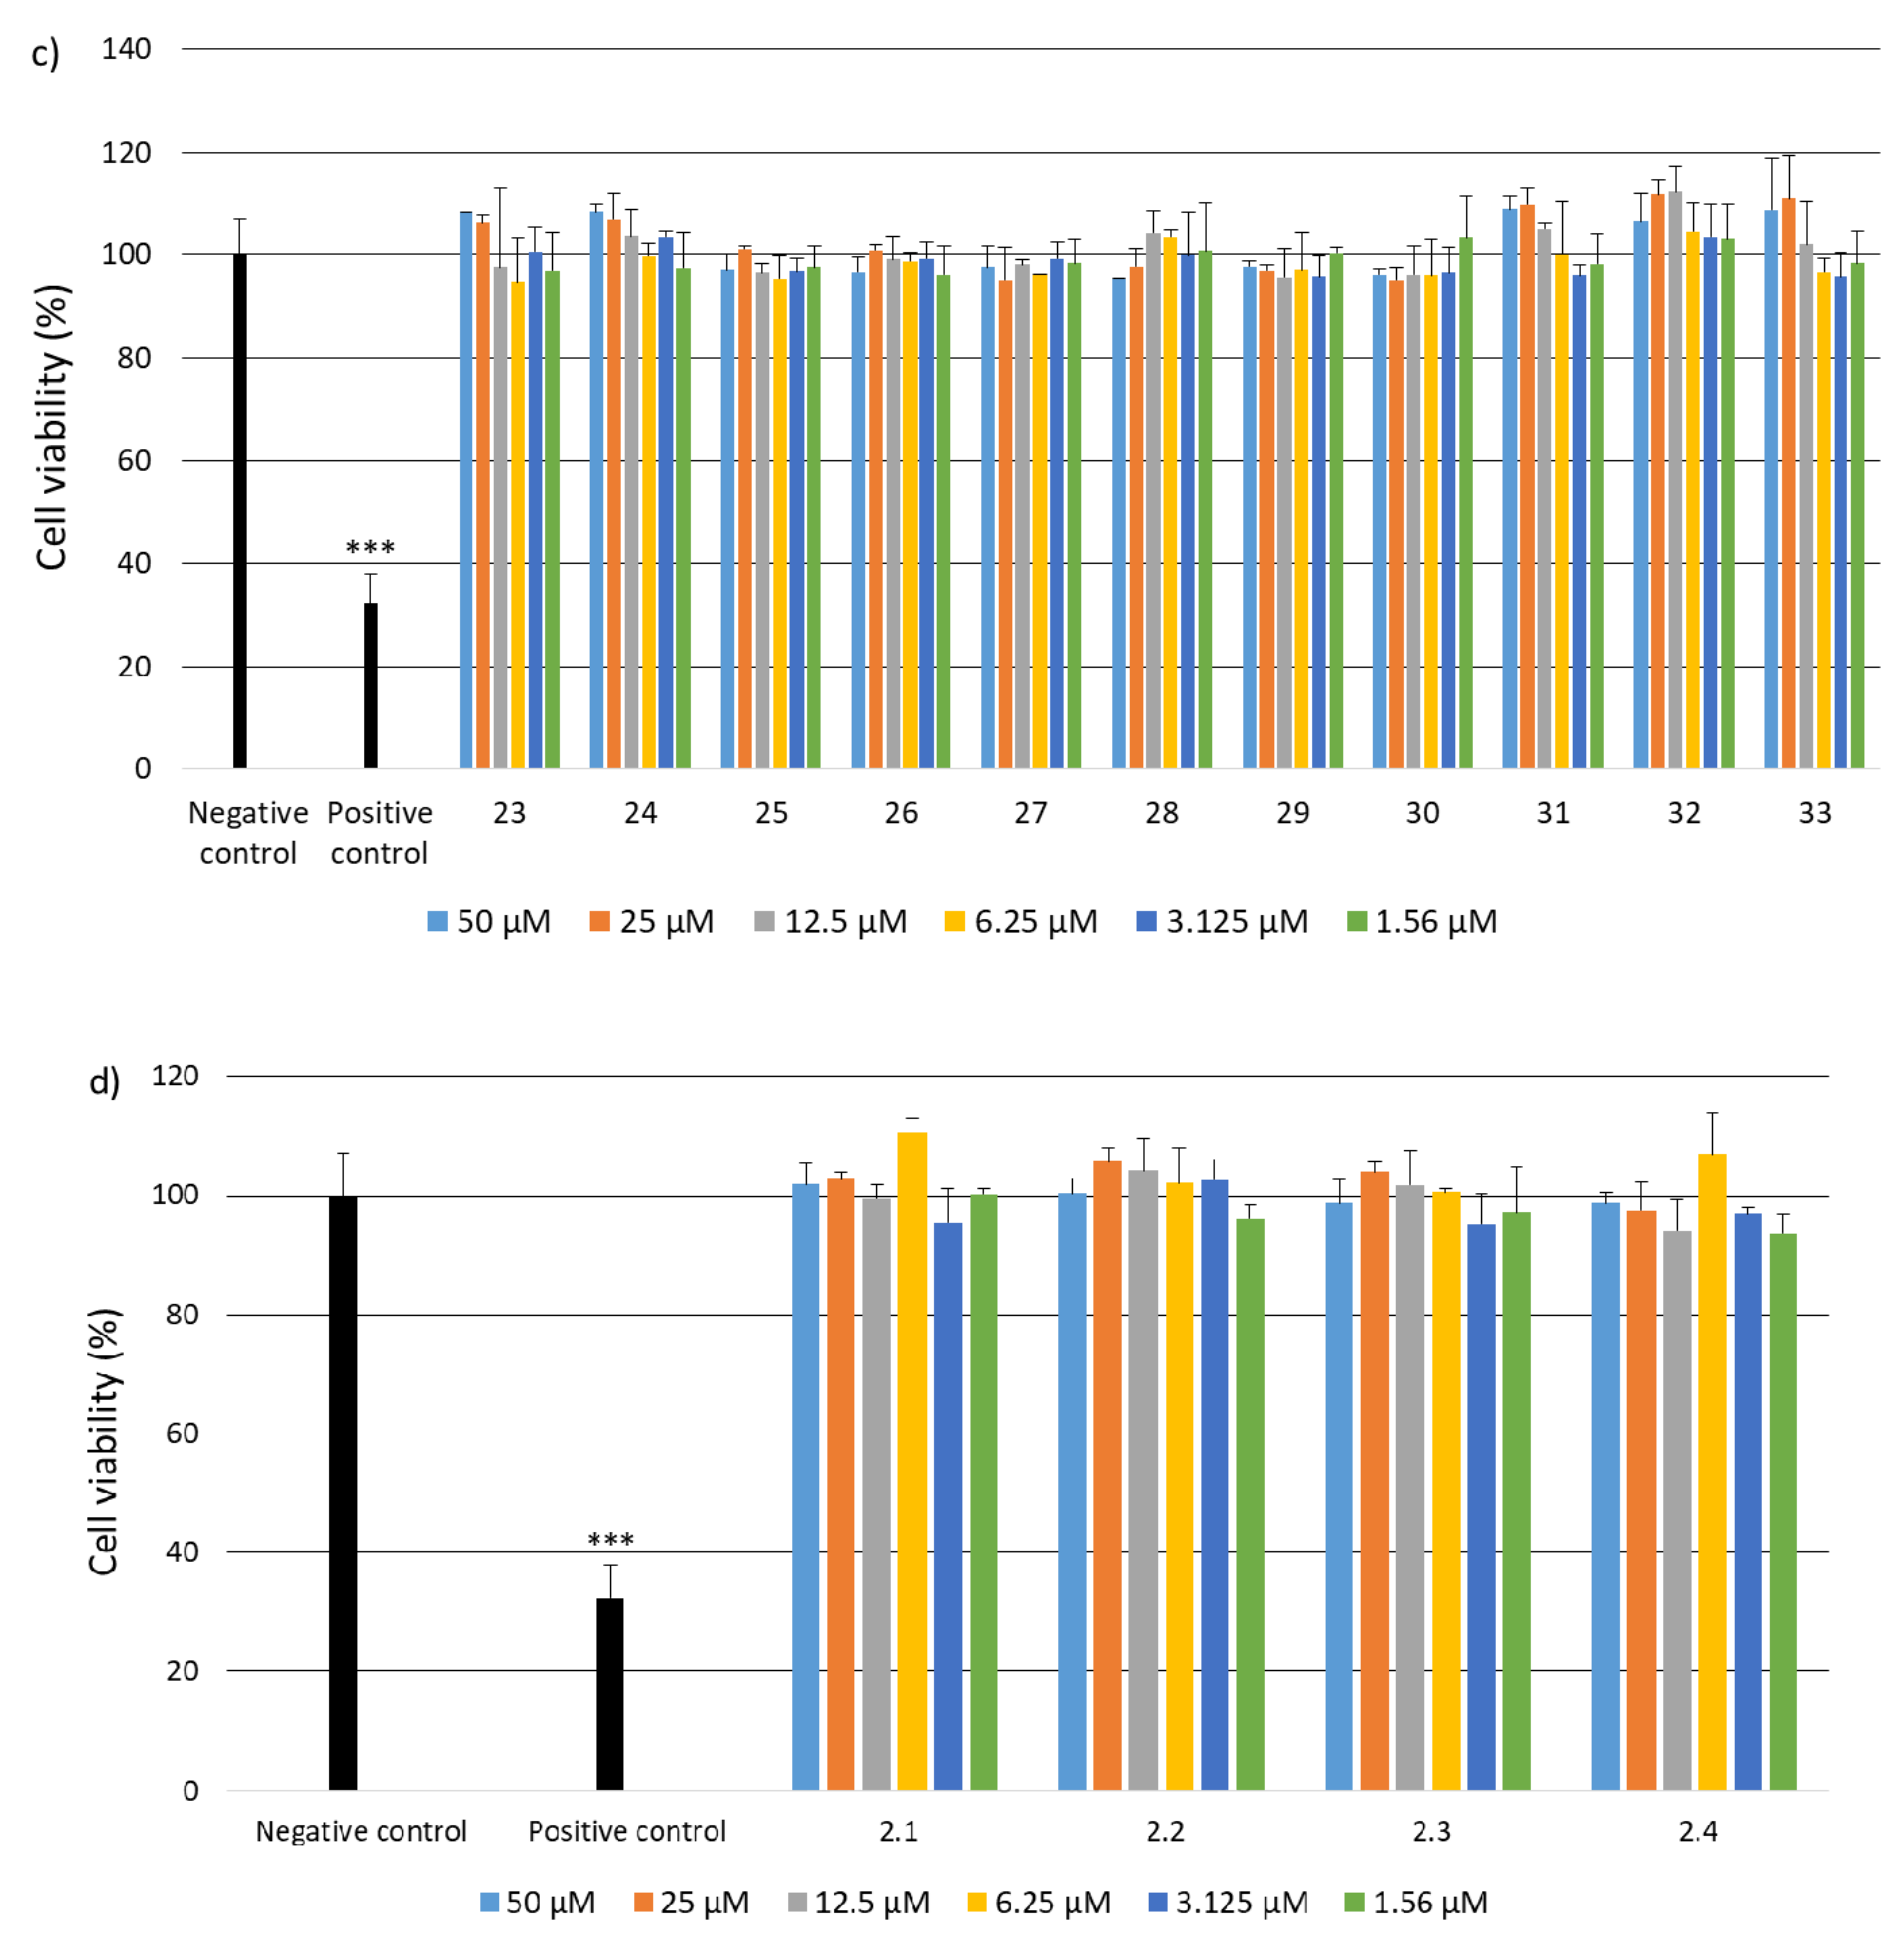

2.2. Research on Biological Activity of Collagen IV Fragments

3.7. Biological Activity Studies

- Cell Viability

- Examination of cytotoxicity of cross-linked porous materials based on the equimolar mixture of peptides 2, 4, 5, 6, 14, 15, 25, 26 and 30